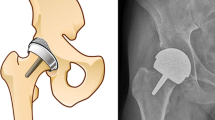

The preferred surgical treatment of FAI is by arthroscopic cheilectomy and -rim-trimming (ACH) (Nwachukwu et al. 2015). Excess bone is removed in the head-neck transition of the femur bone and in the anterolateral region of the acetabular rim. Arthroscopic technique is superior to an open approach based on higher postoperative general health-related quality of life (HRQoL) score (Nwachukwu et al. 2015) and an increased patient satisfaction of 82% (Sansone et al. 2016). Still the main reason for revision after ACH procedure is failure to identify and/or reshape the affected areas in the joint adequately (Heyworth et al. 2007; Ross et al. 2014; Philippon et al. 2007; Larson et al. 2014).

Seven human cadaveric legs including hip joints and hemipelvises, from 4 donors were used in the study (Department of Biomedicine, Aarhus University). The age of the donors ranged between 58 and 94 years, three were from male- and four from female donors. Inclusion criterion was no prior hip surgery, which was assessed by x-ray of the hip and visual inspection for earlier surgical incisions. The study was approved by The Central Denmark Region Committees on Health Research Ethics (Case number 1-10-72-6-16 issued on February 24th, 2016).

The donor legs were scanned in a computed tomography (CT) scanner (Brilliance 64, Philips Healthcare, Cleveland, OH, USA). Settings were 120 kV, 150 mAs, slice thickness 2.5 mm and slice increment 1.25 mm. Bone models were created using an automatic graph-cut segmentation method (Krčah et al. 2011; de Raedt et al. 2013). Bone segmentations of the pelvis included the iliac-, ischial- and pubic bone and for the femur the head down to 5–7 cm distally to the lesser trochanter. All segmentations were visually inspected and verified to be within voxel accuracy (<0.3 mm). Local coordinate systems were created for the bone models by the method described by Wu et al. (Wu et al. 2002).

A portable fixation for the hemipelvises which could be mounted both to the radiology table during recordings and in an operative setting during ACH was constructed (Figs. 1, 2, 3 and 4). Fluoroscopy was made possible from the medial side and used for entering the joint and evaluating the amount of traction applied. Traction was applied using a winch by pulling on a strap around the distal femur. ACH was performed with a 70° wide angle arthroscope, a radiofrequency wand (super multivac 50), burr (5.5 mm barrel burr) and a shaver (dyonics incisor plus), (all surgical equipment was provided by Smith and Nephew, London, United Kingdom). Resection was performed by an experienced arthroscopist with simulation of usual FAI-surgery, allthough the donor hips were not FAI hips by radiological definitions. The surgeon restored what appeared to be normal morphology in accordance with the Danish Hip Arthroscopy Registry (DHAP) (average circumferential area of 116° (SD = 24.5) and a mean depth of 3.8 mm (SD = 1.7) (Lund et al. 2017).

The CT-scans of the separated hemipelvises were aligned with the contralateral side to determine the anatomic coordinate system and subsequently the lateral center-edge angle (CE) and alpha angle were calculated to determine the preoperative degree of FAI by Clinical Graphics (Delft, The Netherlands).

Measurements of CE and alpha-angles revealed that none of the donor hips had a cam-lesion (α < 55°) but showed that two of the donors had a CE > 40° and thereby per definition a pincer-lesion (Table 1).